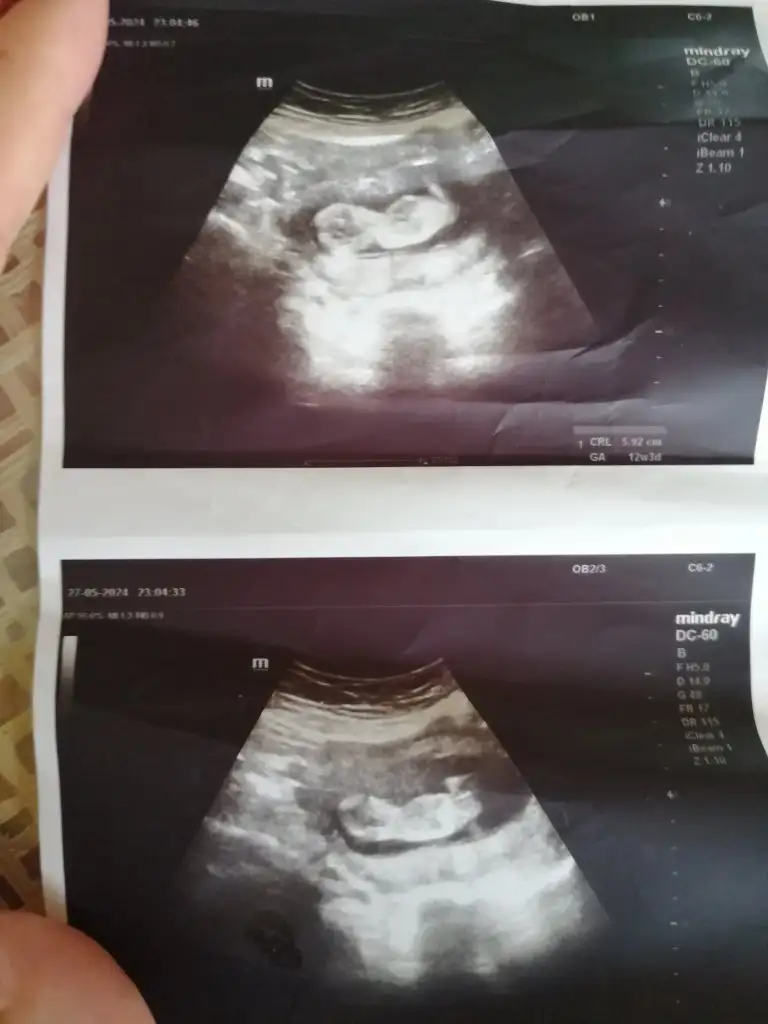

Merhaba 11hafta 4gunluk karından çekilmiş ultrason bende merak ediyorum cinsiyetini